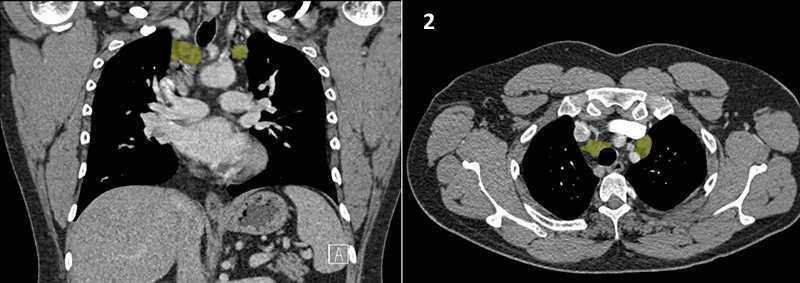

Nodal zones and stations according to the International Association for the Study of Lung Cancer (IASLC) node map.

Table (above): Nodal zones and stations according to the International Association for the Study of Lung Cancer (IASLC) node map. (Source: 1,2) *Depends on the side of the tumour.